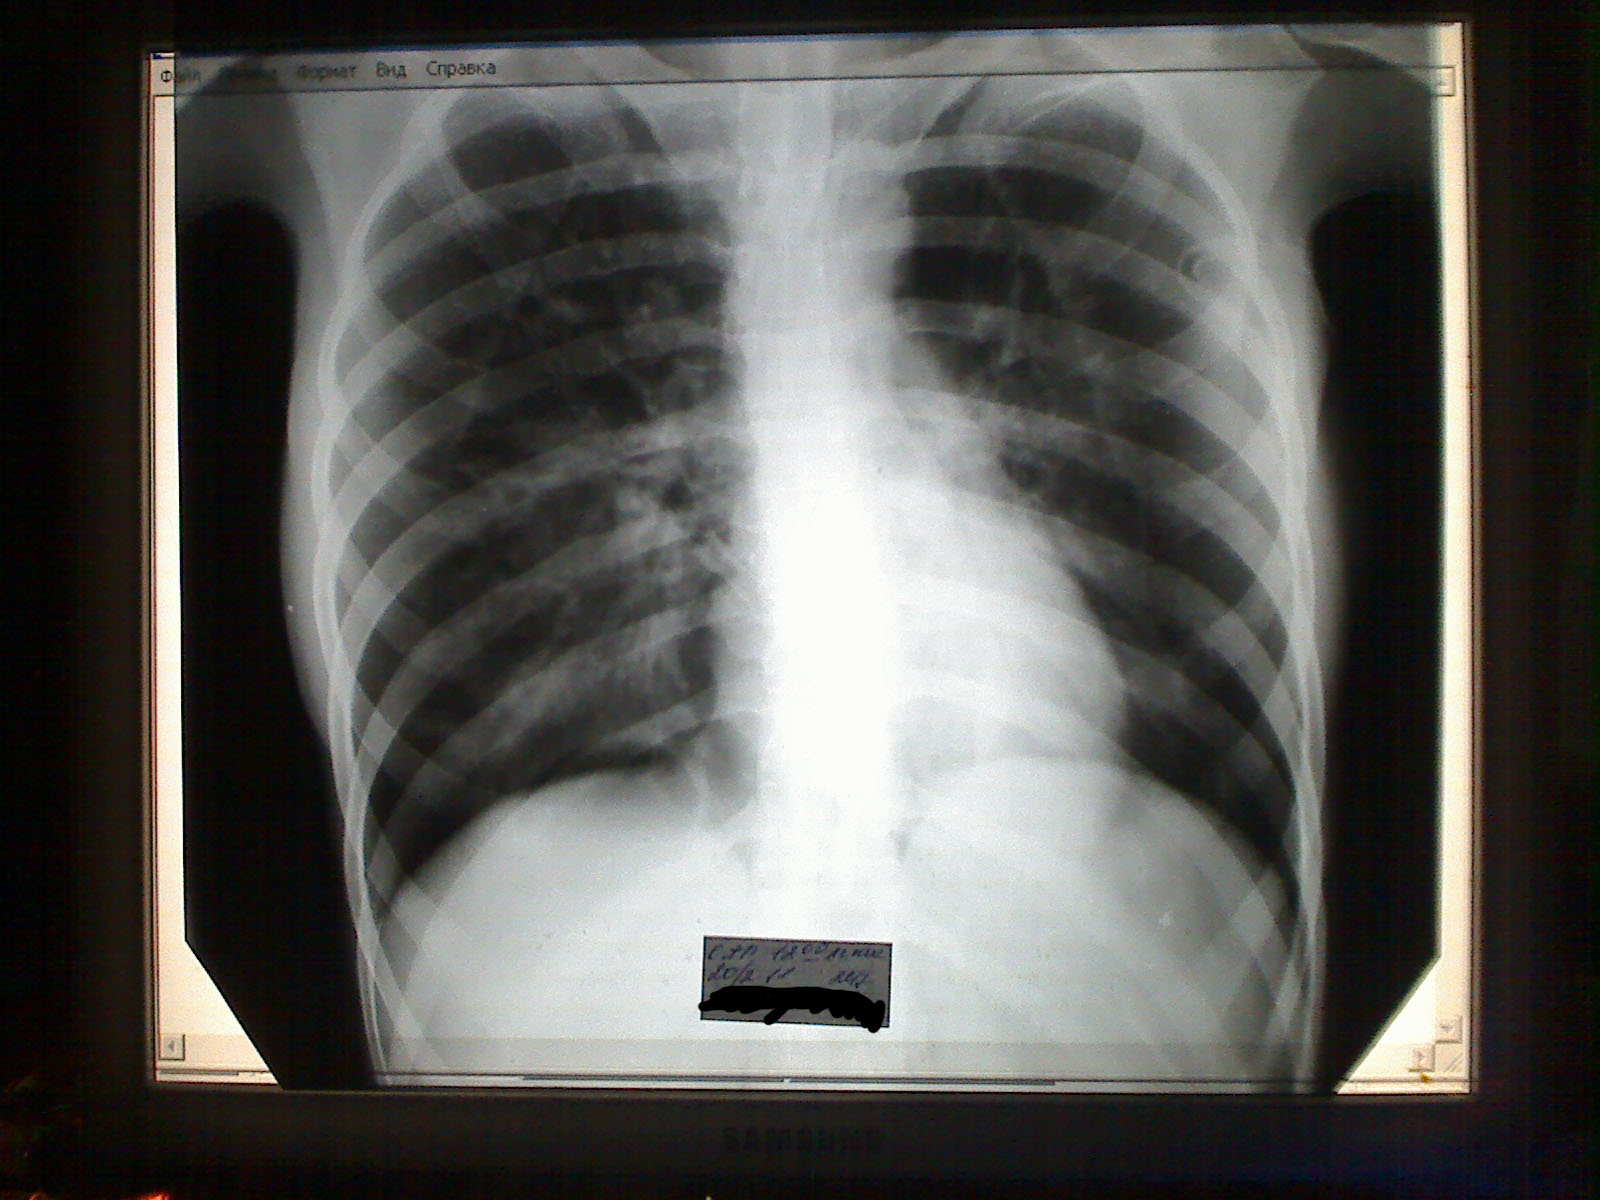

Находилась с 10.02.2011 по 03.03.2011 с внегоспитальной пневмонией на истязаниях в ГКБ № 54 г. Москвы. Все действия производимые надо мною там садистами в белых халатах были насильственны и крайне мучительны. Никакого добровольного информированного согласия на лечение я не подписывала, меня об этом даже никто не просил, ограничившись тем, что получили его от моей мамы, воспользовавшись её на тот момент шоковым состоянием. Разумеется, никто ни о чём её не информировал вообще и даже не собирался. Сама я была в полном сознании практически каждый мой день довольно тяжёлых тех для меня истязаний, едва не закончившихся смертью моей из-за наступивших тяжких последствий – угрозы жизни из-за пневмоторакса, бывшего результатом также насильственно проведённой совершенно ненужной мне операции – трахеостомия. Покинула я сие заведение на инвалидной коляске с анемией средней степени тяжести, в практически предельном уже истощении, подобная жертве Освенцима, к тому же со множество шрамов, дырою в трахее. Мне был причинен существенный моральный и физический вред, т.к. не только непосредственно до поступления туда, в ту больницу со мной не было подобного ничего, но и вообще ещё ни разу в жизни моей!!! На момент поступления я была, фактически, на ногах и гемоглобином в крови даже выше, чем норма. Ещё сутки дышала сама, в  ИВЛ не нуждалась. Но т.к. лечения не было, а были лишь истязания, на второй день уже дышать не смогла, потребовалась интубация и подключение к аппарату искуственной вентиляции лёгких. Обо всё этом подробнее рассказывать долго и нудно, брошу просто несколько ссылок:

Фото и документы